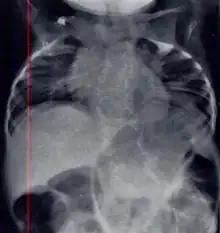

| Radiograph depicting typical skeletal features of Jarcho-Levin syndrome, subtype spondylothoracic dysplasia. Note fanlike configuration of the ribs, with extensive posterior fusion, along with multiple vertebral segmentation defects. | |

Spondylocostal dysostosis, also known as Jarcho-Levin syndrome (JLS), is a rare, heritable axial skeleton growth disorder. It is characterized by widespread and sometimes severe malformations of the vertebral column and ribs, shortened thorax, and moderate to severe scoliosis and kyphosis. Individuals with Jarcho-Levin typically appear to have a short trunk and neck, with arms appearing relatively long in comparison, and a slightly protuberant abdomen. Severely affected individuals may have life-threatening pulmonary complications due to deformities of the thorax. The syndrome was first described by Saul Jarcho and Paul M. Levin at Johns Hopkins University in 1938.[1]

Spondylothoracic dysplasia

Spondylothoracic dysplasia, or STD, has been repeatedly described as an autosomal recessively inherited condition that results in a characteristic fan-like configuration of the ribs with minimal intrinsic rib anomalies. Infants born with this condition typically died early in life due to recurrent respiratory infections and pneumonia due to their restricted thorax.[3][4][5] Recently, a report[6] has documented that actual mortality associated with STD is only about 50%, with many survivors leading healthy, independent lives.